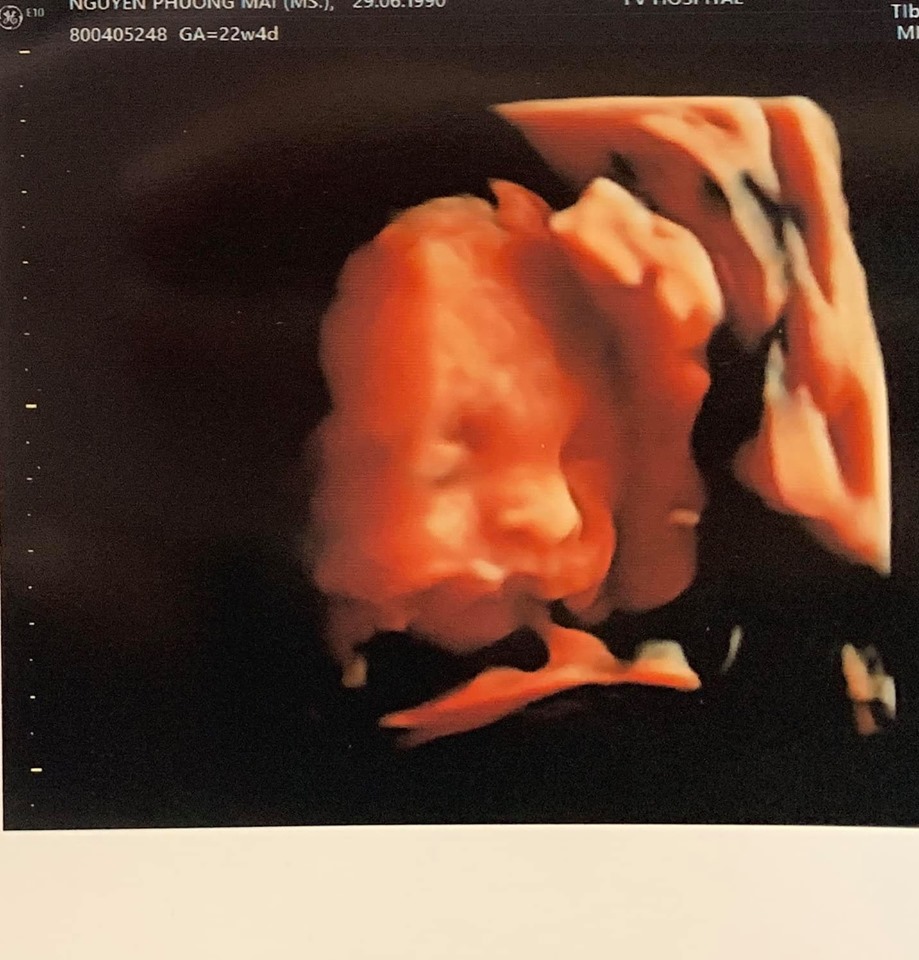

Cô còn khoe luôn cả ảnh siêu âm đứa con đầu lòng của mình